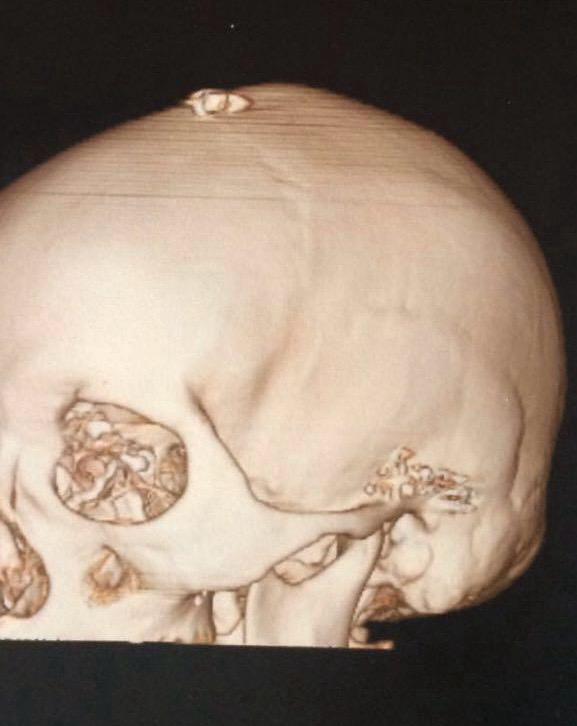

Rănită și în stare de șoc, femeia a fost dusă la spital. „Am ajuns prima victimă la spitalul unei baze NATO. În ziua aceea, medicii din Paris era în grevă, dar în câteva minute s-au mobilizat exemplar. După zece minute, au început să vină ambulanțele — orașul era complet blocat, în alertă de grad zero. Au venit medici de acasă, inclusiv psihologi și specialiști în psihiatrie. Am aflat mai târziu că la 21:30 se dăduse ordin să se tragă în mai multe puncte din Paris, mai ales în intersecții. Eu aveam glonț în vârful capului. Se oprise la câțiva milimetri de creier. Era foarte fierbinte, simțeam cum mă arde, dar mă bucuram că simt, că asta însemna că trăiesc. Eram plină de sânge, curge continuu. Fetele din mașină au crezut că am murit. Medicii m-au întrebat dacă vreau anestezie ca să mi-l scoată, am zis că nu.”, își amintește Cezara.

„Câtă durere am văzut acolo… Intrau în sală și ieșeau acoperiți, morți, adică. A fost cumplit. Pereții erau plini de lumini pe care le puseseră medicii ca să citească radiografiile, se vedeau gloanțele cum luceau pe radiografii. Lângă mine era un bărbat cu o gaură în mână, o fată ciuruită în trei locuri. Îți dădeai seama când mureau oamenii, după cum urlau de durere. Medicii au spus că am vorbit în patru limbi, dar eu nu-mi amintesc. Mi-au făcut transfuzii de sânge, mi-au scos resturile de glonț pe viu și mi-au pus șase capse.”